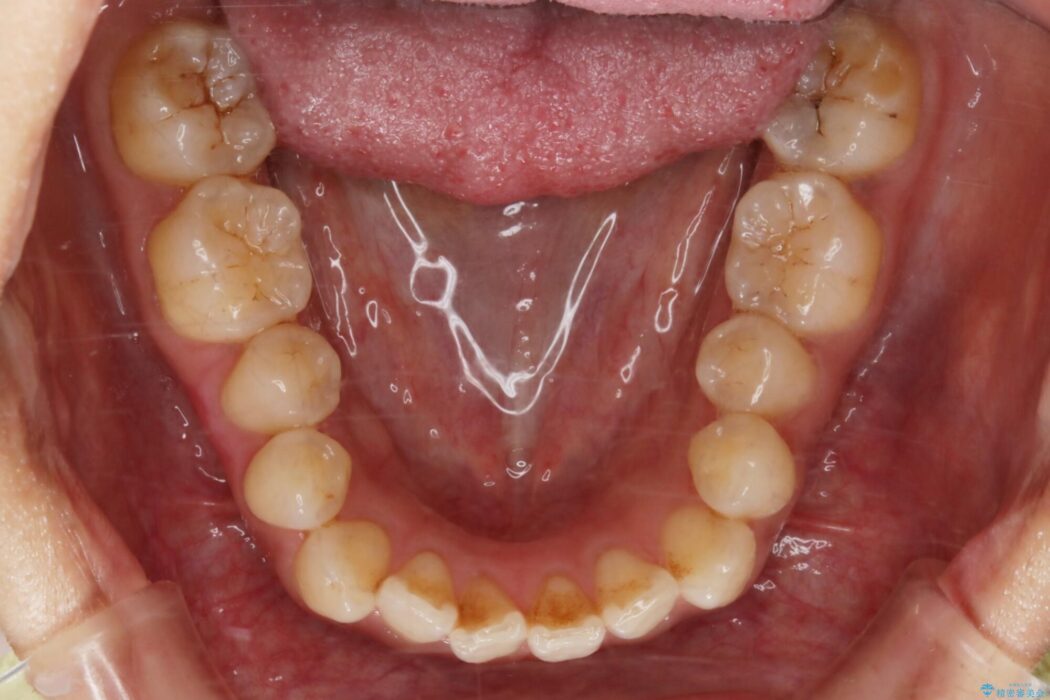

【20代女性】開咬の隙間と歯列の凸凹をまとめて改善する

開咬により上下の噛み合わせが悪く、歯列の凸凹も合わせて治療したいとのことで来院されました。

なるべく非抜歯にて治療をするためインビザライン(マウスピース)とマイクロインプラントを併用した治療を行いました。

マウスピースとマイクロインプラントの併用により矯正するための隙間を確保し、治療期間は長くなりますが非抜歯できれいな歯列弓を得ることができます。